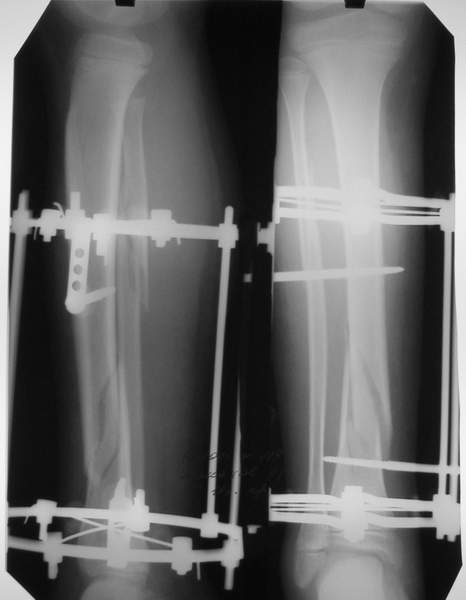

3a

3b

3c

В аттачте № 3 - один из примеров полукольцевого аппарат...

Это уже я баловался.

Итог? Работы больше (по времени и

интраоп "подгонке"), срастается также, а особого преимущества по сравнению с

"чиста" кольцевым (вес, удобство ношения и пр.) - я, по крайней мере,

не нашел.

Теперь не балуюсь.

Может быть зря?

МТ мы используем, конечно, не только на голени. В прилагаемом примере у парня при поступлении была наружная ротация 40 гр. и "полумертвый" коленный сустав. Можно был бы, конечно, до конца использовать полную компоновку. Но для того он и есть метод выбора.